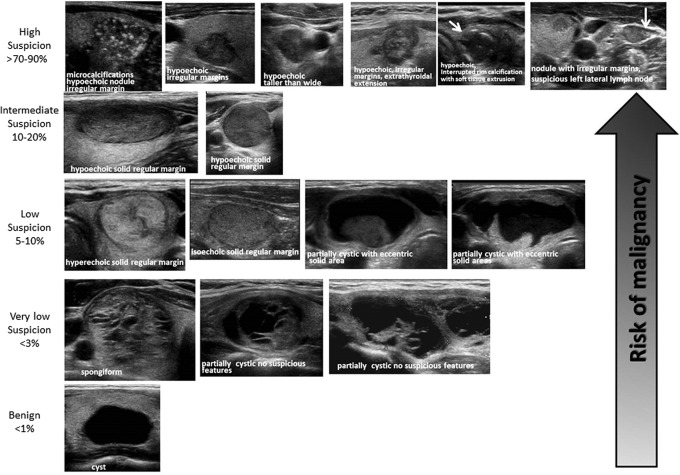

- American Thyroid Association (ATA) visual patterns:25

- Figure 40. ATA Nodule Sonographic Patterns and Risk of Malignancy (Used with permission. License no: 4463231228489)